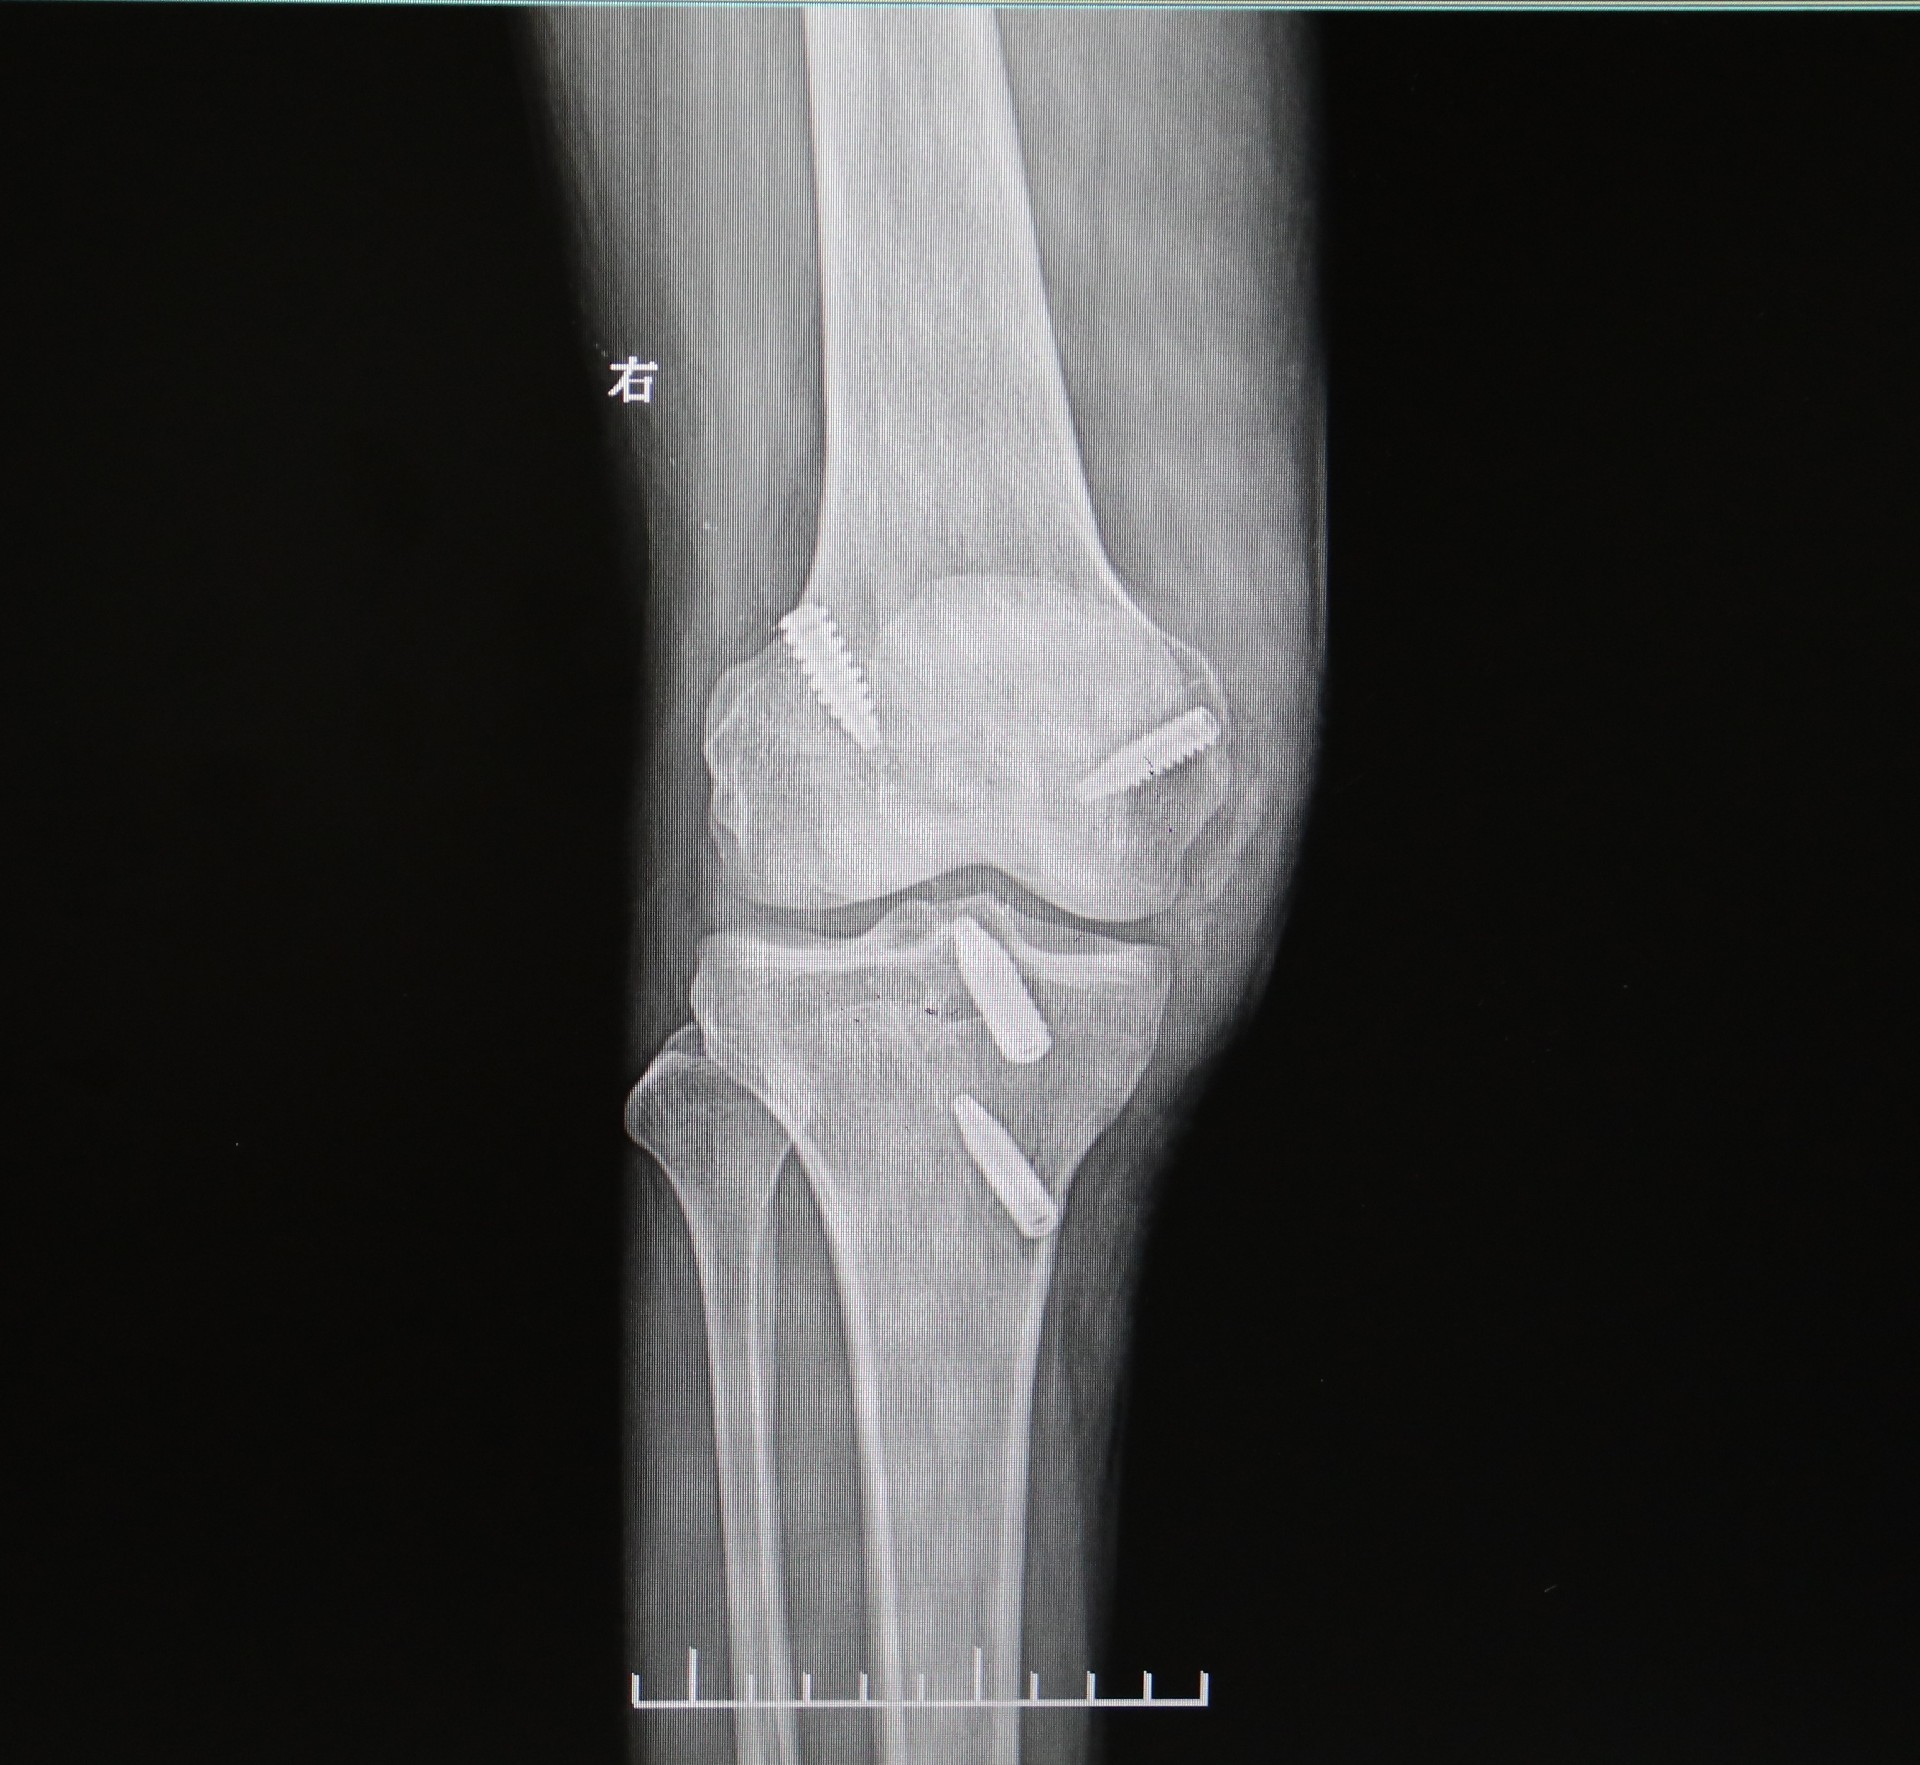

面对复杂的伤情,周武忠主任团队为他在麻醉下实施“关节镜下右膝关节交叉韧带重建+半月板成形术”。手术顺利完成。